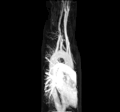

Arteria lusoria in der MR-Angiographie, MIP. Animiertes GIF, 4,26 MB.